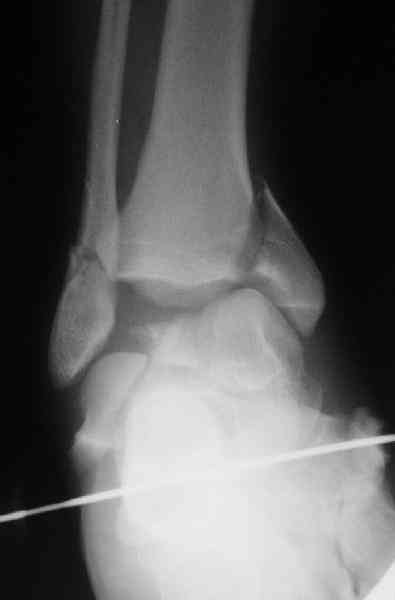

Re: повреждение таранной кости

повторили рентгенограммы и доделали проекции, к единому мнению все еще не пришли